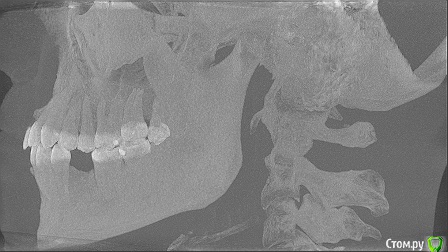

marilinka Опубликовано 4 июня, 2015 Поделиться Опубликовано 4 июня, 2015 Добрый вечер, уважаемые стоматологи!На данный момент верхняя челюсть 1 зуб, 16 под удаление......хотелось бы имплантировать, но очень боюсь, что близко к гайморовой пазухе.....в данном случае, а именно в верхней челюсти, не обойтись без синуслифтинга?И как лучше его делать непосредственно при удалении или по прошествии какого то времени?Нижняя челюсть, первичная адентия(надеюсь правильно выразилась)двух пятерок, зубов там нет даже не помню сколько лет, но лет 15-17 точно, была у 2 хирургов и оба говорят, что в местах отсутствующих зубов очень большие промежутки, то есть для 1 зуба много места, а для 2 мало.Мне бы самой очень хотелось восстановить на данный момент нижний ряд, т.к. состояние рядом находящихся зубов меня очень беспокоит. Насколько вообще возможна там имплантация, хватит ли костной ткани, возможно ли с помощью ортодонта чуть-чуть сдвинуть зубки, чтобы был 1 полноценный зуб, а не полтора? Какое время эта процедура займет?Еще 1 хирург сказал, что по моей челюсти вообще плачет ортодонт, что все у меня криво, челюсти разные и верхняя челюсть выпирает, что все это нужно исправлять....честно первый раз такое услышала...Какие варианты-схемы имплантации возможны в моем случае?Очень надеюсь на советы. На врачей в своем городе к сожалению не могу понадеяться, была у 2 и об обоих не сложилось впечатление достаточно компетентных врачей в этом вопросе. Ссылка на комментарий

marilinka Опубликовано 5 июня, 2015 Автор Поделиться Опубликовано 5 июня, 2015 а вот так...поизвращалась как могла Ссылка на комментарий